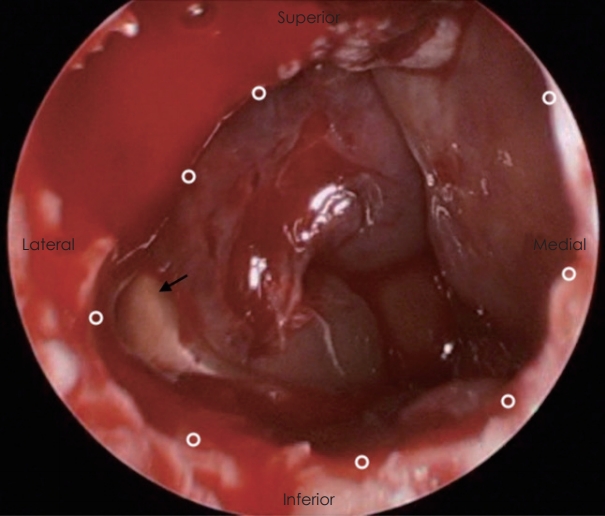

58세 여자 환자가 내원 2일 전부터 시작된 두통과 가벼운 비회전성 어지럼증으로 본원 신경과에 내원하였다. 환자는 기저 질환이 없이 건강하던 자로 두통은 간헐적으로 머리 전반적인 부위에서 발생한다고 하였고, 신경학적 검사상 이상소견은 보이지 않았다. 말초성 현훈 감별 위해 두부충동 검사, 두위충동 검사, 두위안진, 냉온교대 온도안진 검사(bithermal caloric test) 등을 시행하였으나 특이 소견은 관찰되지 않았다. 이에 추가 정밀 검사 및 보존적 치료를 위해 신경과로 입원하였다. 일반 혈액 검사에서 백혈구는 10.07×103/uL에 중성구 81%, 적혈구 침강속도는 86 mm/hour로 증가되었으나 그 외 검사상 다른 이상 소견은 보이지 않았다. 뇌 확산 자기공명영상(brain MR diffusion)을 촬영하였고, 허혈성 병변 및 뇌실질의 병변은 확인되지 않았으나, 우측 사골동과 접형동 부비동염 의심 소견이 확인되었다. 입원 2일째 환자가 갑작스러운 복시와 우측 안검하수를 호소하여 시행한 안과 검진상 시력, 안압 등은 정상이었고, 안구 운동 시 우안의 내전, 외전, 상전, 하전 제한과 안검하수가 관찰되었다(Fig. 1). 우측 사골동과 접형동 부비동염 및 우측 동안 및 외전 신경 마비 의심하에 부비동 전산화단층촬영(paranasal sinus CT, PNS CT) 및 후두와 자기공명영상(posterior fossa MRI)을 시행하였다. MRI에서 팽윤된 양측 해면정맥동과 주변 경막의 비후 소견이 관찰되었으며, 상기 소견은 우측이 더 심하였고 혈전 형성은 보이지 않았다(Fig. 2). PNS CT상 우측 전두동, 상악동, 사골동과 접형동의 연부조직음영이 있었으며, 좌측 상악동, 사골동과 접형동에도 일부 음영증가 소견이 보였고, 골결손은 보이지 않았다(Fig. 3). 환자는 코막힘, 후각 감퇴, 콧물, 재채기 등의 비증상은 호소하지 않았으나, 비강 검사상 좌측 비중격 만곡증 및 양측 비용 소견이 관찰되었다. 임상학적 양상과 영상 소견을 종합한 결과 급성 부비동염에 병발된 해면정맥동혈전염으로 인한 우측 동안 및 외전 신경마비로 의심되어 부비동 내시경 수술과 항생제와 스테로이드 정맥주사(ampicillin/sulbactam 1.5 g tid, cefotaxime 1 g tid, metronidazole 500 mg tid, dexamethasone 5 mg bid)를 진행할 것을 계획하였다. 입원 3일째, 전과 후 비중격 교정술과 양측 부비동 내시경술을 시행하였다. 전신마취하에 비중격 교정술 후 우측 전두동, 상악동, 사골동의 비용과 병변 점막을 제거하면서 자연공을 충분히 넓혔으며, 접형동 개구술을 통해 배농을 시행하였다(Fig. 4). 좌측 사골동, 상악동, 접형동도 비용과 병변 점막 제거 및 개방술을 진행하였다. 술 후 1일째, 두통, 어지럼증과 안검하수는 호전되었으나, 복시는 지속되는 양상이었다. 술 후 5일째에 안검하수 증상은 개선되었고, 우측 주시시 여전히 복시를 호소하였다. 술 후 7일째 퇴원하고 경구 항생제, 경구 스테로이드, 비강 스테로이드제(amoxicillin/clavulanate potassium 1 g bid, prednisolone 10 mg bid, fluticasone 5 mg qd)를 3주간 사용하였다. 추적 관찰하기 위해 촬영한 PNS CT상 양측 상악동, 사골동과 접형동의 부비동염 양상은 대부분 호전되었다(Fig. 5). 술 후 1개월째 안과 진료를 통해 복시가 개선된 것으로 확인되었고, 수술 2개월경 시행한 안과 검진상에서 외안근 기능이 모두 정상화된 것을 확인할 수 있었다(Fig. 6).